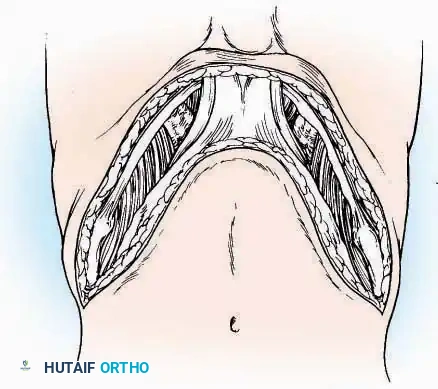

U Approach

Indications: Extensive plantar fasciotomy, radical tumor resection, or complex osteomyelitis debridement requiring access to the entire plantar surface of the calcaneus.

Positioning: Prone, with the leg supported on a large sandbag.

Surgical Technique:

* Incision: Join the medial and lateral approaches described above to form a large, continuous U-shaped incision around the posterior four-fifths of the calcaneus.

* Flap Elevation: Deepen the incision directly to bone. Elevate a massive plantar flap consisting of skin, the specialized fatty heel pad, and the plantar fascia. Retract this flap distally to expose the entire plantar calcaneal tuberosity.